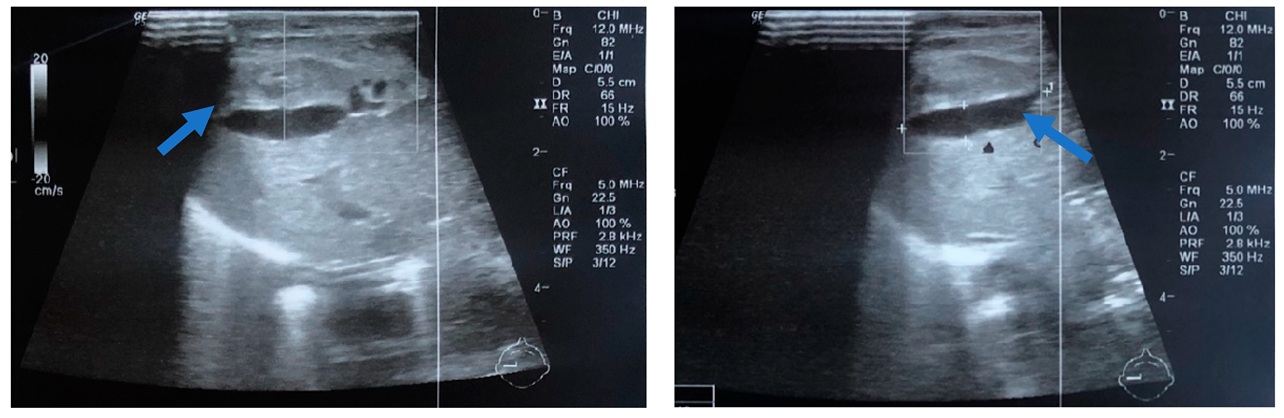

2.1. Case 1

2.2. Case 2